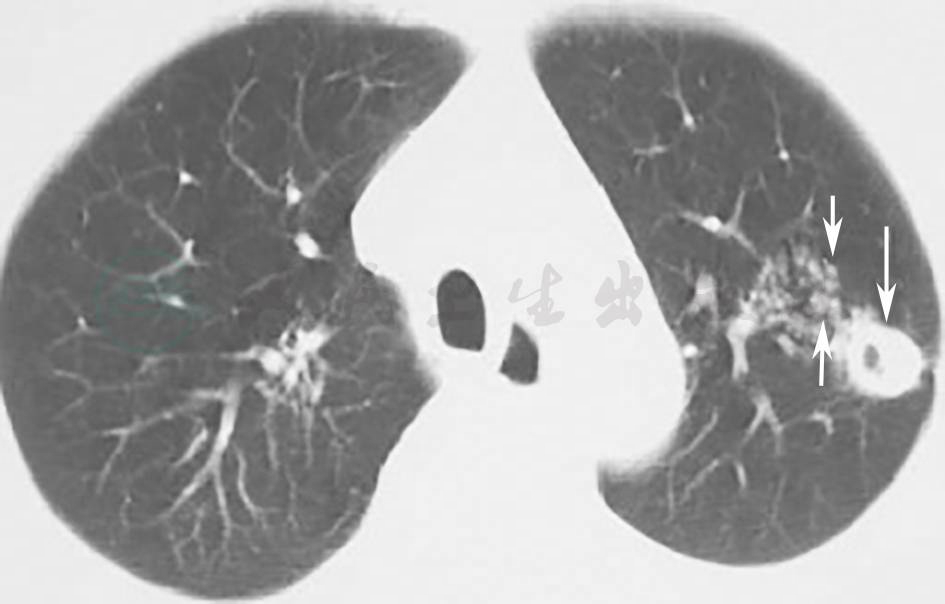

患者有发热、体重下降等全身症状,有咳嗽等呼吸系统症状,胸部影像学表现为左肺上叶实变影。肺结核好发部位为双肺上叶和下叶背段,胸部影像可出现渗出、实变及空洞影等(图8)。因此,对于本例患者,需要进一步排查结核病。

图8 肺结核胸部影像学表现

胸部CT可见发生于肺上叶的结核病变,空洞伴卫星灶(箭头)